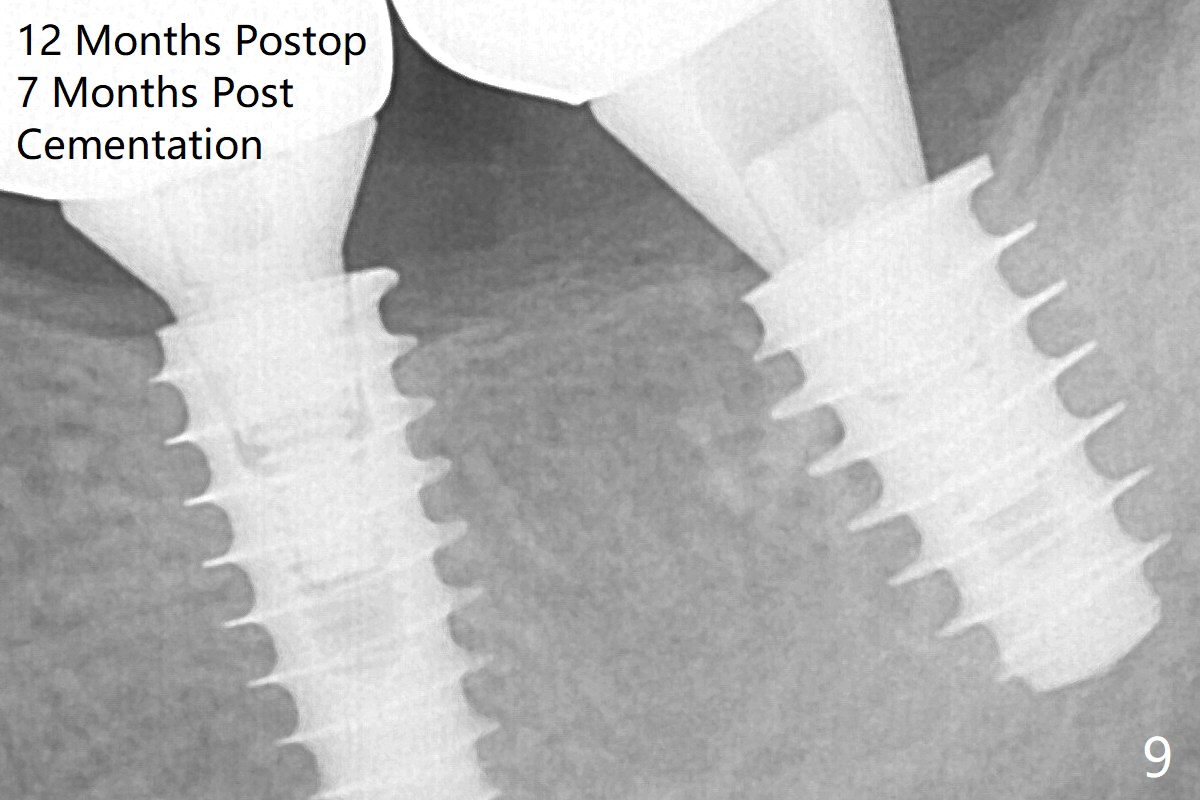

The implant at #19 could be placed more mesially (Fig.4 (*: Vera Graft)). The implants seem to have osteointegrated 4.5 months postop (Fig.5). The bony trabeculae form between the 2 implants crestally 12 months postop, i.e., 7 months post cementation (Fig.9).